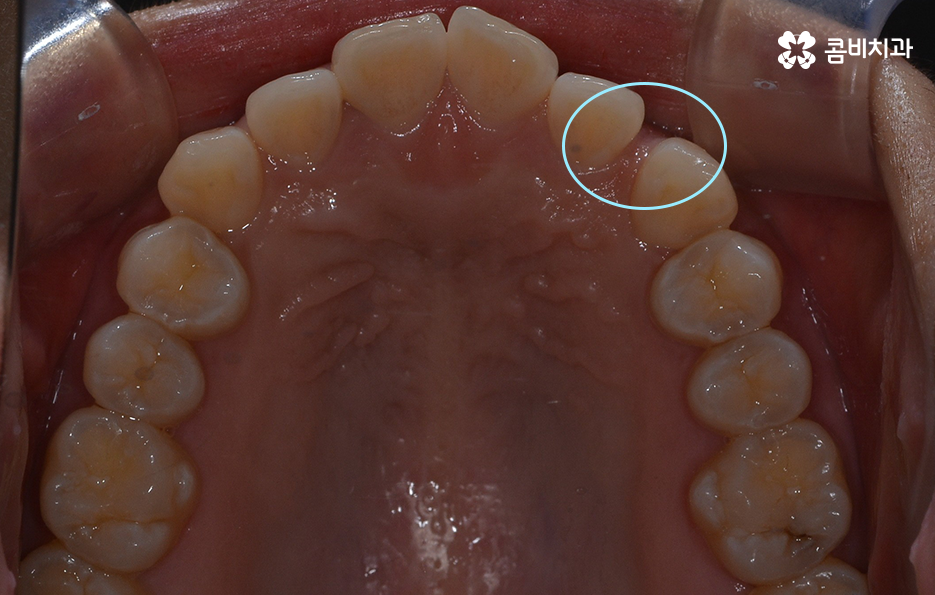

이 중에서는 발치 여부에 대해서도 많은 고민이 되는 부분 중에 하나일 거예요. 교정 치료에서 발치를 하는 경우에는 보통 작은 어금니를 발치하여 치아의 이동 공간을 확보하는 경우가 많은데 아무래도 생니를 발치한다는 생각에 발치는 무조건 안좋다고 느끼거나 거부감을 느끼시는 분들도 많이 있어요.

교정 치료는 크게 발치와 비발치치아교정으로 나뉠 수 있는데 비발치치아교정의 경우에는 아무래도 치아가 움직이는 양도 적고 그에 따라 교정 기간도 짧은 편에 해당되고 있어요.

그렇기 때문에 비발치치아교정이 좋다고 생각하기 보다는 개인에 따라서는 치아의 이동 공간 확보를 충분히 하기 위해 발치가 필요한 경우도 있고 얼굴 변화나 부정교합의 개선을 위해 발치가 필수적인 경우도 있을 거예요

단순히 비발치치아교정이 발치를 안해도 되니 무조건 좋다고 판단하기 보다는 각 개인의 치료 목적과 구강 및 골격, 얼굴형의 상태를 종합적으로 정밀 검진하여 자신에게 적합한 치료 계획을 잘 세우는 것이 중요하다고 강조드리고 있어요